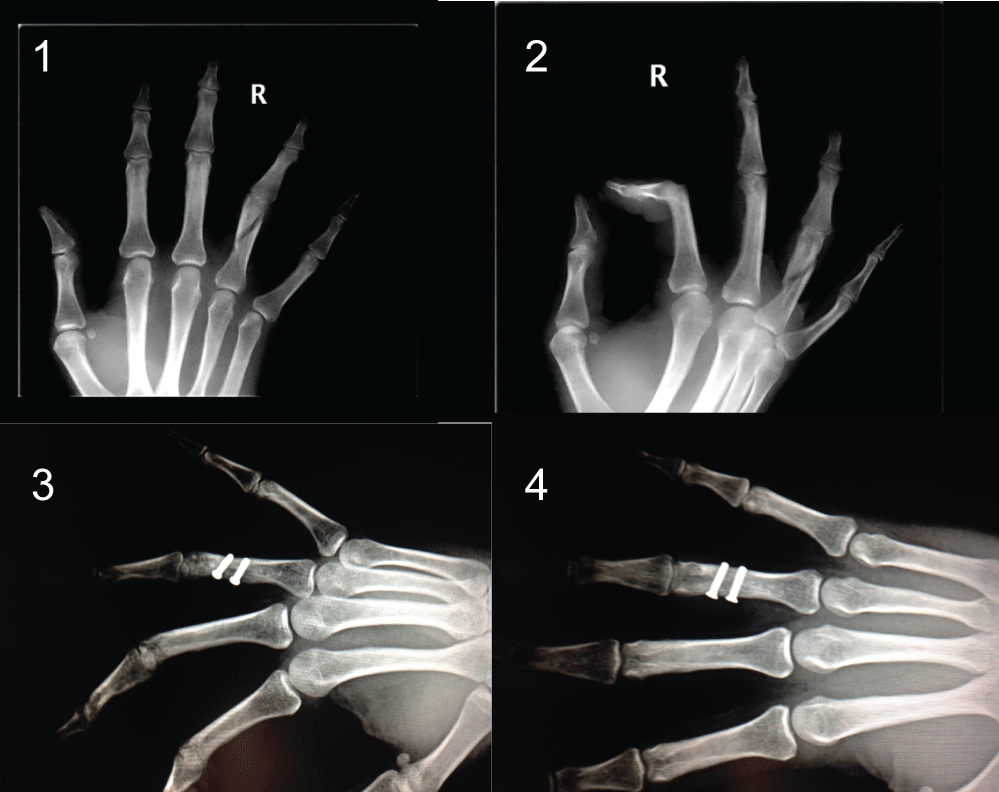

The number of screws used for osteosynthesis depended greatly on the fracture pattern. Thirteen (14%) fractures were treated with a single screw; 51 (54.8%) fractures with 2 screws; 29 (30.1%) with 3 screws; and 1 (1.1%) fracture was treated with 4 screws (Figure 2).

Figure 2: Fracture of the proximal phalanx (3rd finger) treated using 4 percutaneous screws.View Figure 2

The most frequent type of fracture was the long oblique fracture, found in 40 (43%) cases. The second most frequent was the spiral fracture, in 14 (15.1%) cases (Figure 3).

Figure 3: Spiral fracture of the middle phalanx (3rd finger) treated using 2 screws. View Figure 3